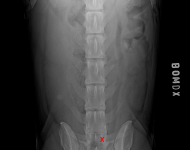

MVDr. Meloun: Lumbosakrální přechodový obratel